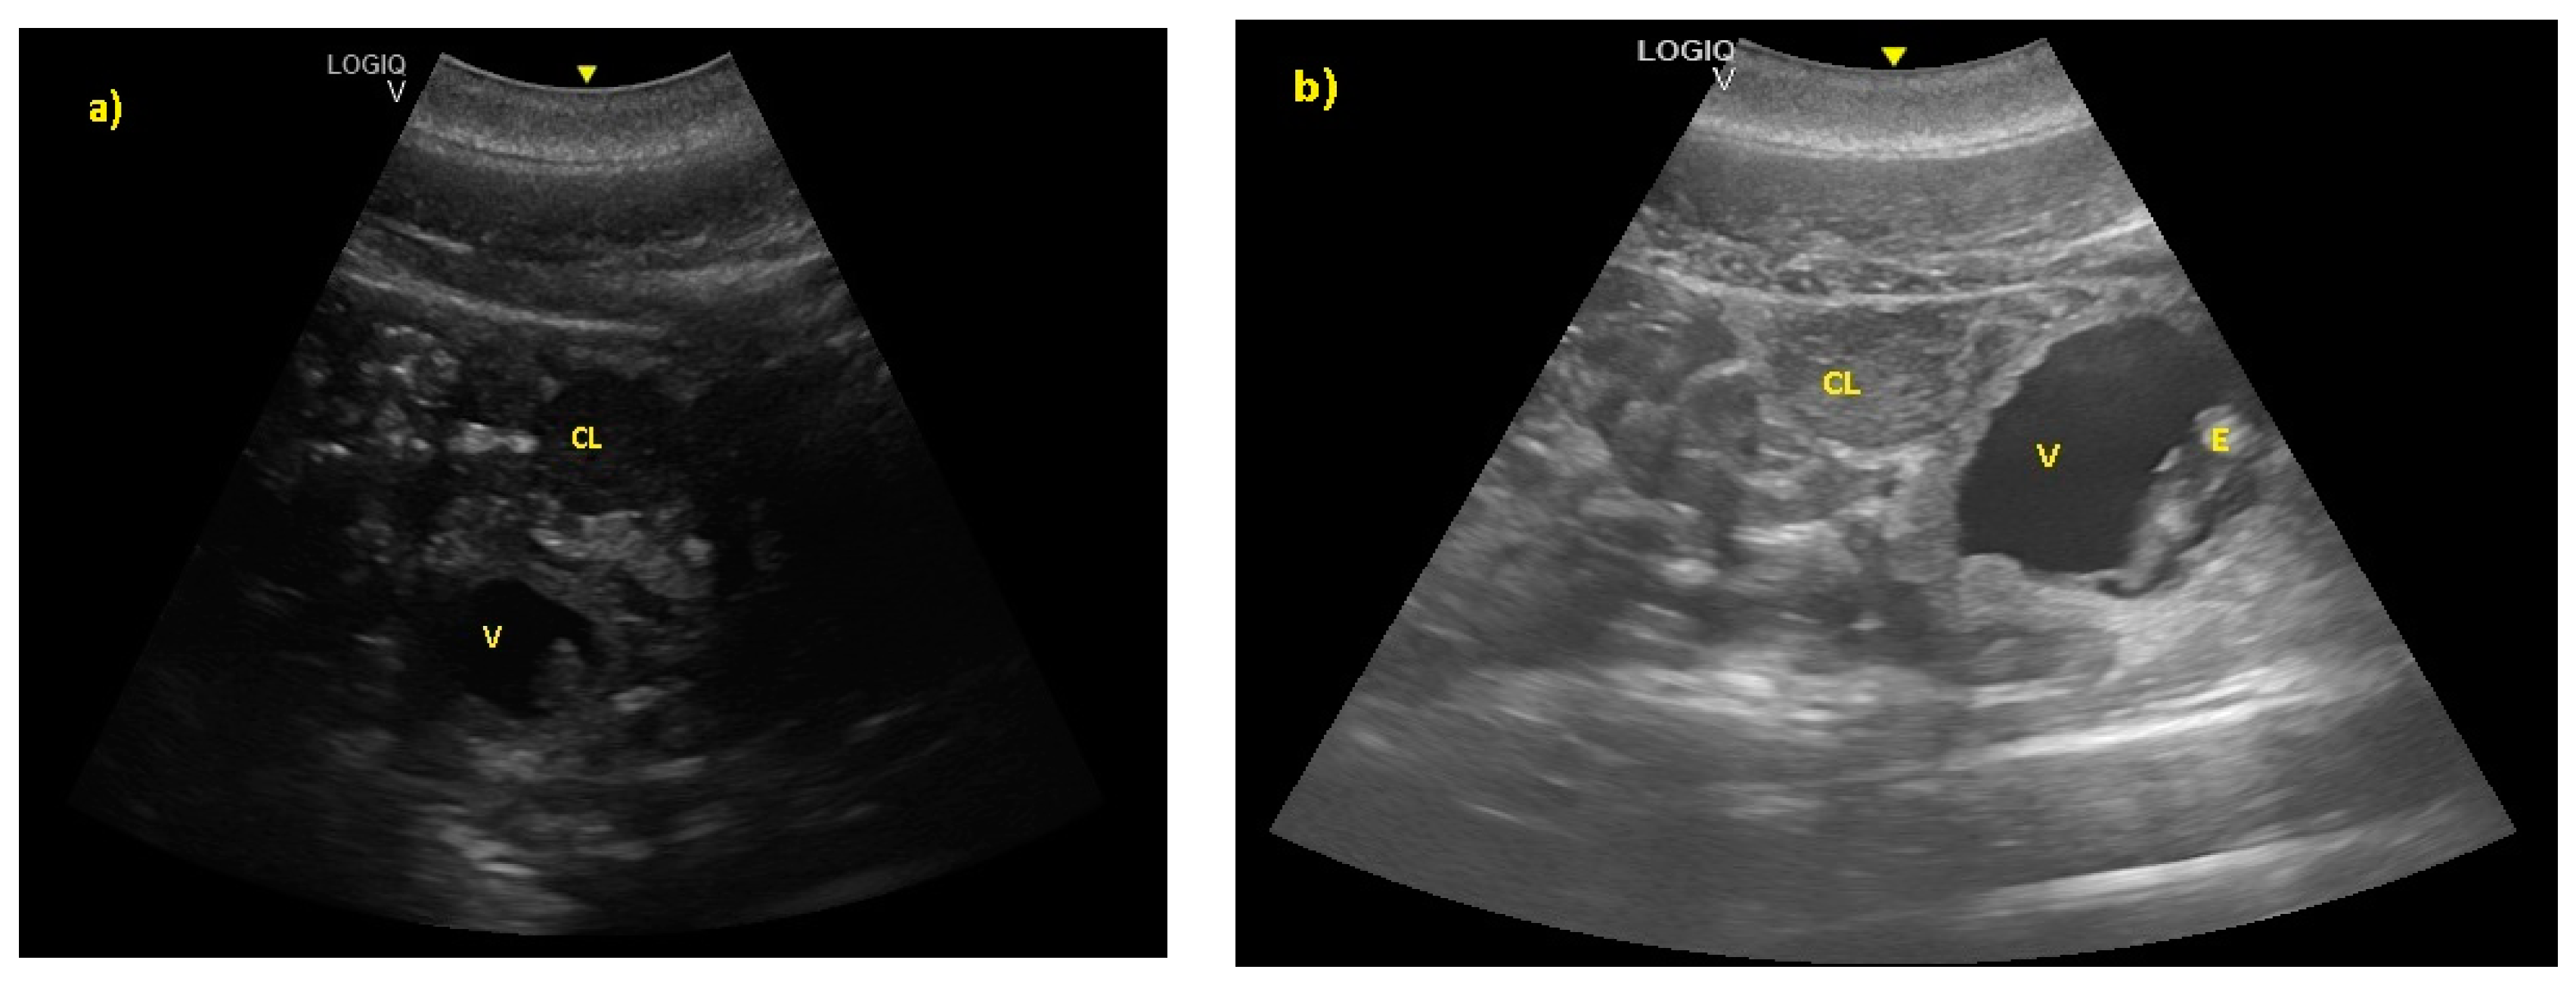

- Ivančič, M.; Gomez, F.M.; Musser, W.B.; Barratclough, A.; Meegan, J.M.; Waitt, S.M.; Llerenas, A.C.; Jensen, E.C.; Smith, C.R. Ultrasonographic findings associated with normal pregnancy and fetal well-being in the bottlenose dolphin (Tursiops truncatus). Vet. Radiol. Ultrasound 2020, 2020, 1–12. [Google Scholar]

- Williamson, P.; Gales, N.J.; Lister, S. Use of real-timeB-mode ultrasound for pregnancy diagnosis and measurement of fetal growth rate in captive bottlenose dolphins (Tursiops truncatus). J. Reprod. Fertil. 1990, 88, 543–548. [Google Scholar] [CrossRef]